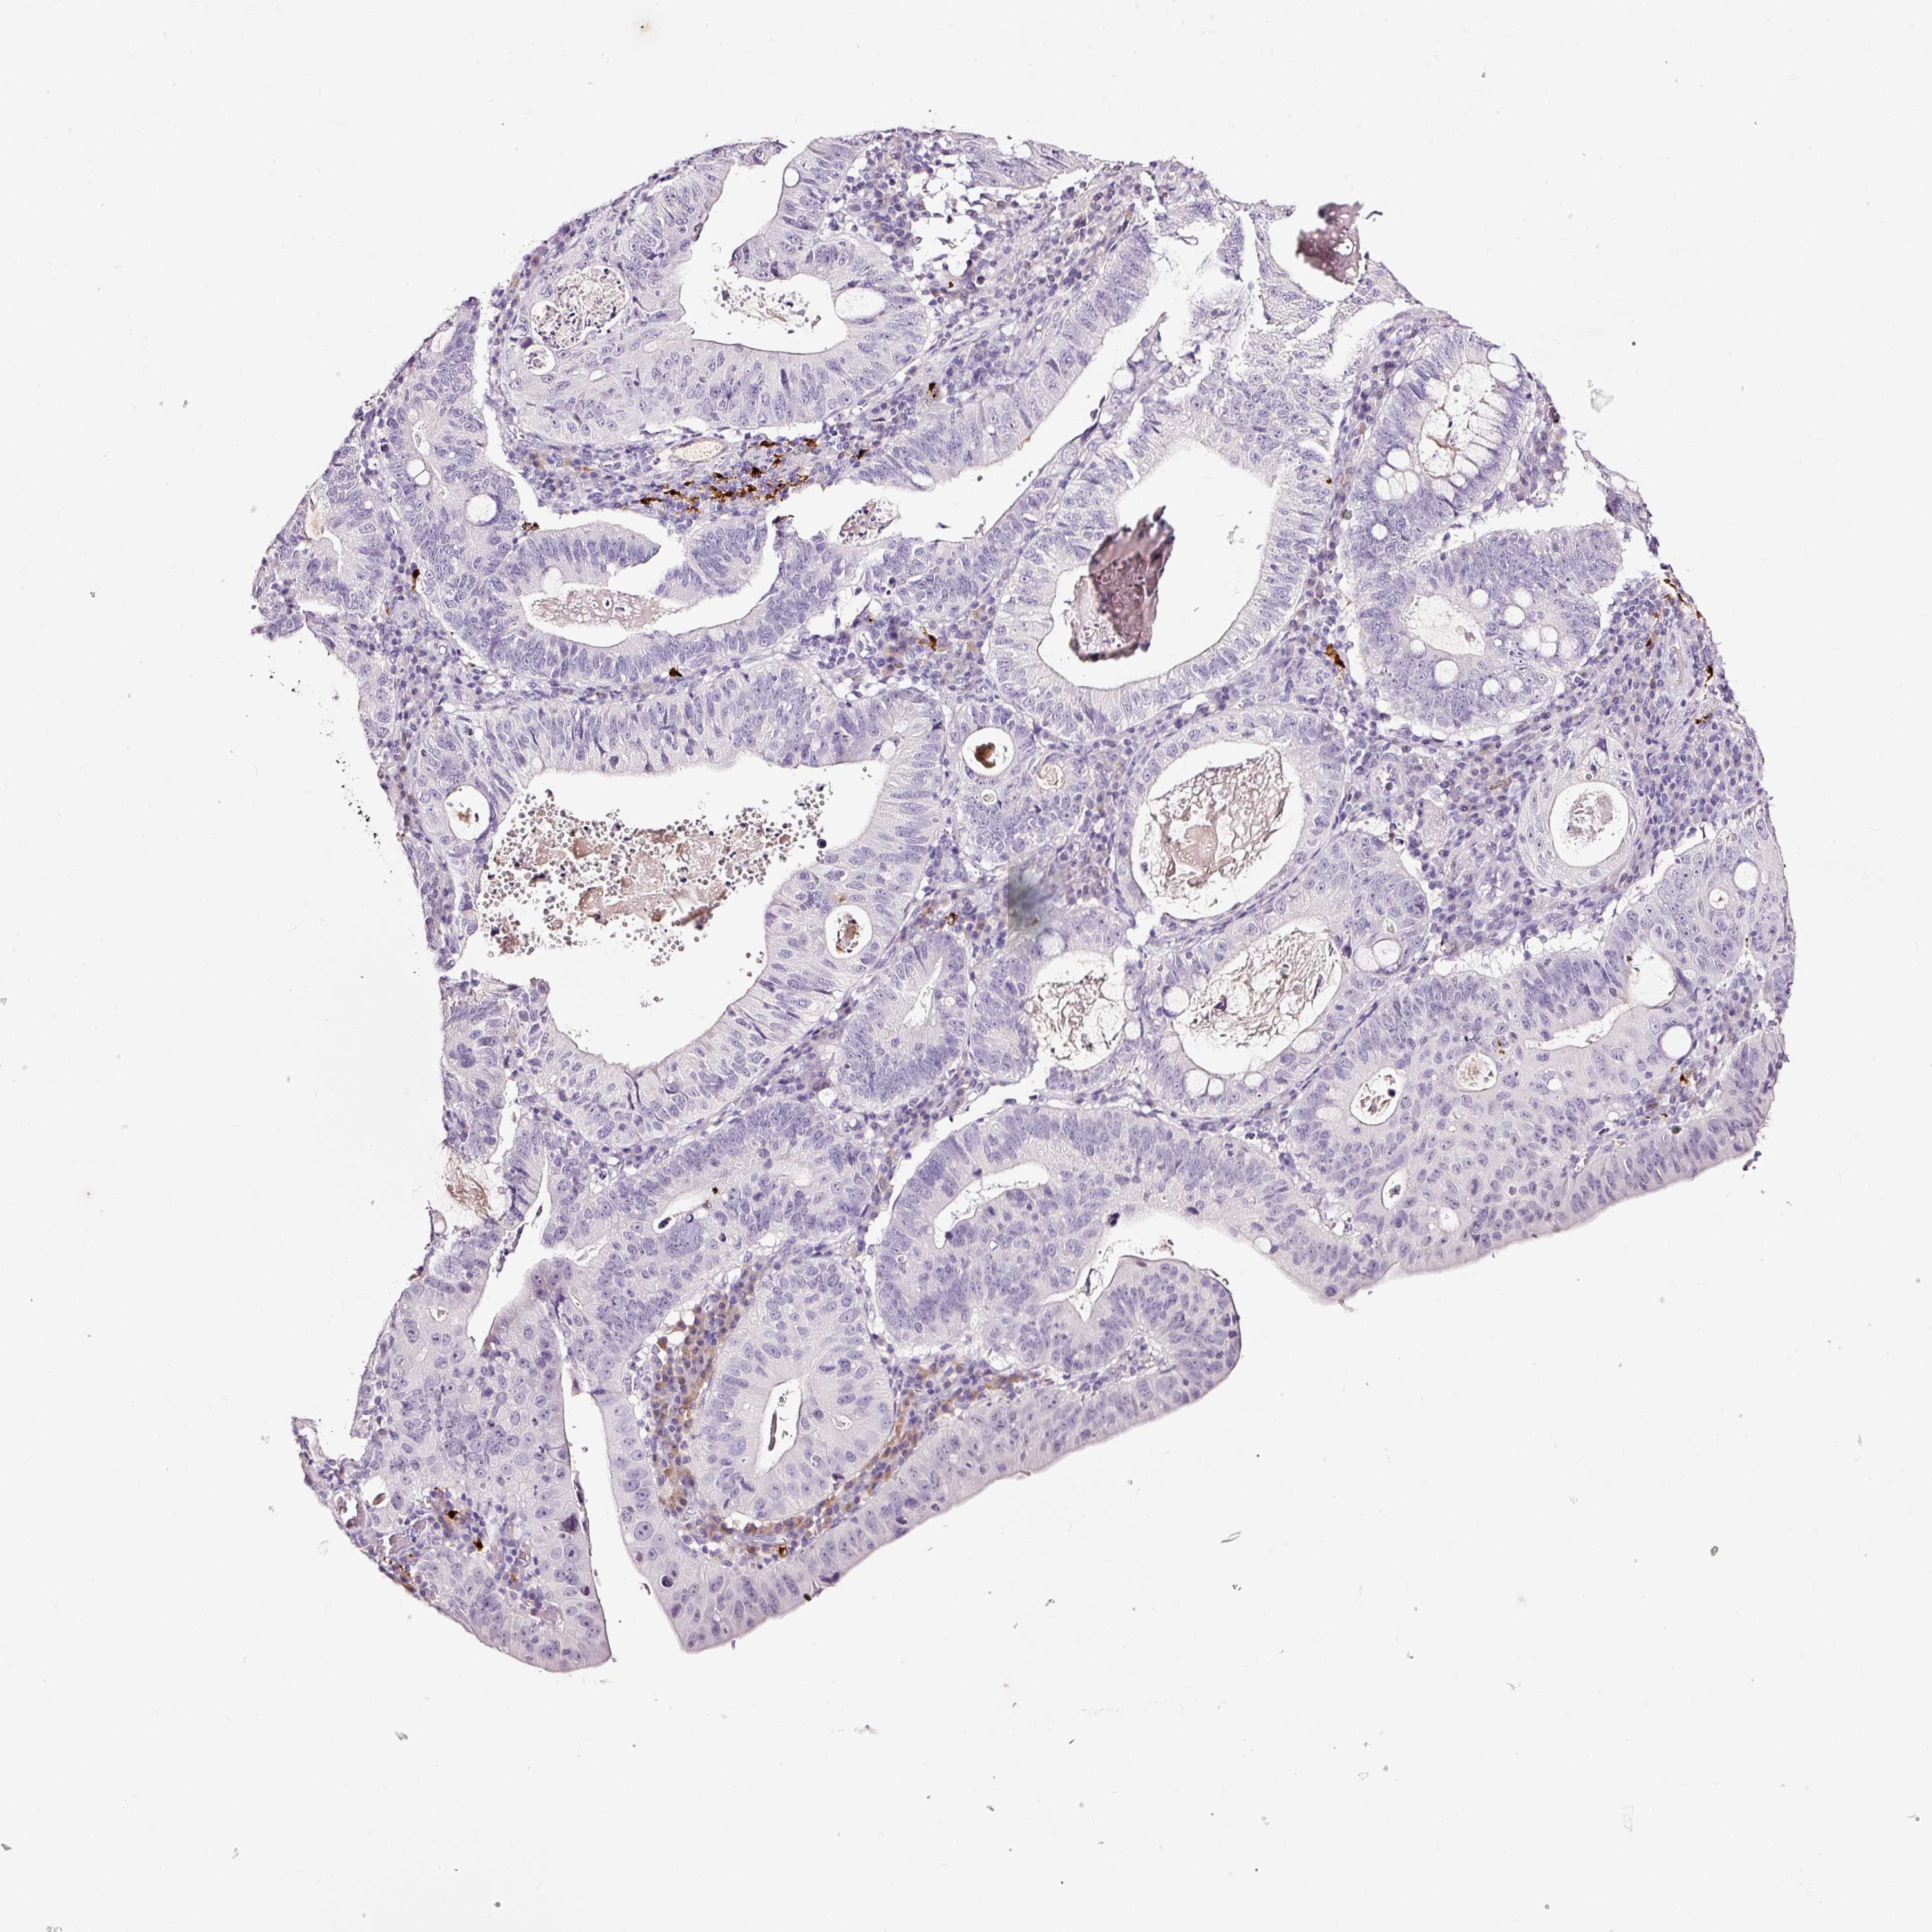

STOMACH CANCER - Protein expressioni

A mouse-over function shows sample information and annotation data. Click on an image to view it in a full screen mode. Samples can be filtered based on level of antibody staining by selecting one or several of the following categories: high, medium, low and not detected. The assay and annotation is described here.

Note that samples used for immunohistochemistry by the Human Protein Atlas do not correspond to samples in the TCGA dataset.

Antibody stainingi

Antibody staining in the annotated cell types in the current human tissue is reported as not detected, low, medium, or high, based on conventional immunohistochemistry profiling in selected tissues. This score is based on the combination of the staining intensity and fraction of stained cells.

Each image is clickable and will lead to virtual microscopy that enables deeper exploration of all samples and also displays staining intensity scores, fraction scores and subcellular localization as well as patient and tissue information for each sample.

Antibody HPA051467

Antibody CAB025133

Staining

High

Medium

Low

Not detected

Intensity

Strong

Moderate

Weak

Negative

Quantity

>75%

75%-25%

<25%

None

Location

Nuclear

Cytoplasmic/membranous

Cytoplasmic/membranous,nuclear

Adenocarcinoma, NOS